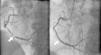

On physical exam, heart rate was 102 beats/min and blood pressure was 103/87 mmHg. The rest of the clinical exam was unremarkable with normal S1, S2 and no murmur. The ECG revealed sinus rhythm, left axis deviation, non-specific intraventricular conduction block and ST-T wave abnormalities suggestive of inferior ischemia. Laboratory tests revealed an elevated troponin I level of 11.8 ng/ml. A two-dimensional (2D) echocardiogram showed severe inferior wall hypokinesis, with moderately reduced left ventricular systolic function and estimated ejection fraction of 35–40%, with no significant mitral regurgitation (MR). The patient was urgently taken to the cardiac catheterization laboratory and was found to have a 99% RCA lesion (Figure 1), with no significant lesions in the other vessels. Successful percutaneous coronary intervention with stenting of the RCA was performed (Figure 1); the patient was admitted to the telemetry floor for close monitoring, and continued on intravenous normal saline to prevent contrast-induced nephropathy.